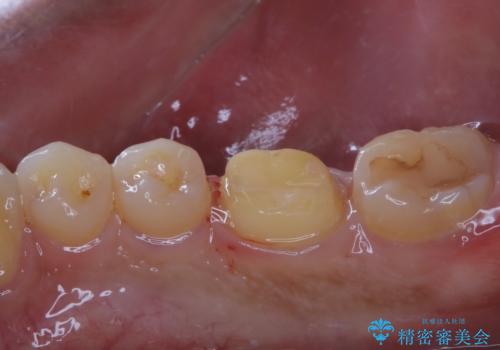

- セラミックへのやり替えを希望された患者様です。

日常的に食いしばる癖があり、歯の表面にはエナメルクラック(歯の表面にできる細かい破折線)も複数認められたため、セラミッククラウンによる治療をご提案しました。

適合不良の補綴物は二次的な虫歯発生のリスクが高まります。

自費診療で用いられる材料は保険適応の材料に比べて、より精密で適合の良い被せ物作ることができるため、長期的な虫歯のリスクを大幅に減らすことが可能です。